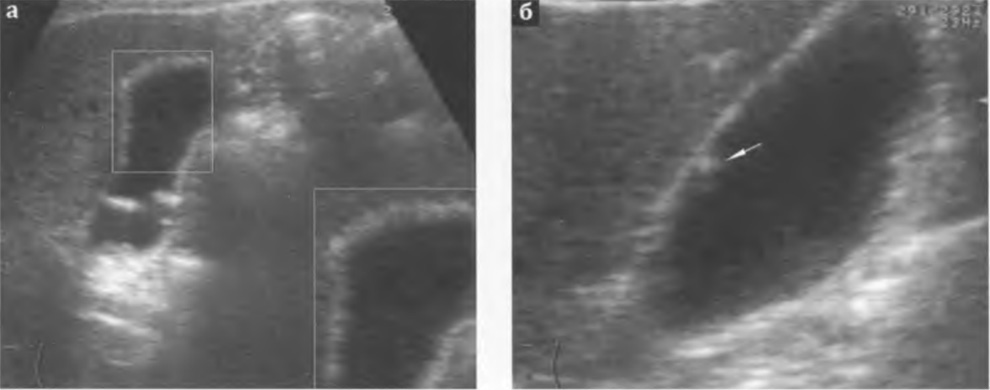

Конкременты. Ультразвуковым признаком конкремента желчного пузыря является гиперэхогенная структура в его просвете, смещаемая при изменении положения тела, дающая эффект дистальной акустической тени (рис. 3.1а-е).

Обычно камни лоцируются на задней стенке желчного пузыря или свободно перемещаются в его полости. Конкременты менее 0,2 см не образуют дистальной акустической тени, что затрудняет их диагностику.

При крупных камнях за счет эффекта бокового рассеивания их ультразвуковые размеры могут быть меньше истинных размеров. Мелкие камни попадают в тень от крупных и не визуализируются. В случае, когда камни заполняют весь желчный пузырь, его просвет не визуализируется. От его передней стенки идет широкая акустическая тень, закрывающая заднюю стенку пузыря (рис. 3.2а,б).

Рис. 3.1а,б,в,г,д,е. Варианты ультразвукового изображения и расположения конкрементов в желчном пузыре: г - конкремент в гартмановском кармане; д,е - конкремент в шейке желчного пузыря.